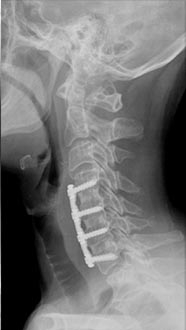

56 year old woman who presented with severe neck pain with numbness of both hands and balance problems due to severe cervical stenosis. Patient underwent C4 to C7 anterior cervical discectomy and fusion with complete resolution of her neurological symptoms.